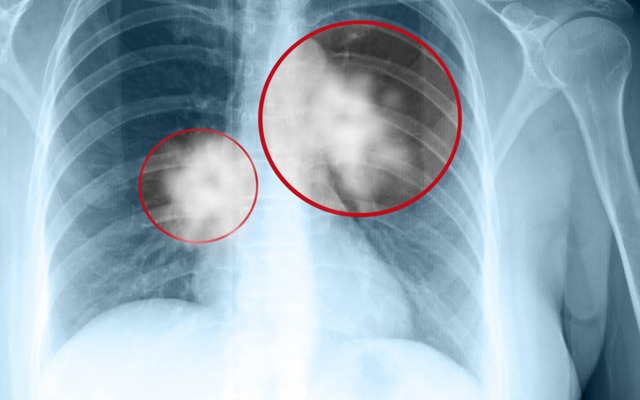

Cầm tờ chẩn đoán "UT biểu mô tại chỗ" của cậu con trai Xiao Chen 8 tuổi, anh Wang (Phúc Kiến, Trung Quốc) cảm thấy đất trời sụp đổ. Mọi chuyện bắt đầu từ lần khám sức khỏe định kỳ. Con trai mới khỏi sau lần cảm lạnh dẫn tới viêm phổi nên anh lo lắng, muốn chụp CT. Chỉ là kiểm tra lại cho yên tâm, ai ngờ lại nhận được kết quả UT phổi.

Anh Wang nhìn vào những nốt kính mờ trên phim chụp mà lòng như lửa đốt. Anh không giữ được bình tĩnh, suýt chút nữa thì làm loạn cả bệnh viện đòi phẫu thuật cho con. Đến khi được bác sĩ từ tốn giải thích kỹ, anh mới vỡ lẽ. Vừa ôm con trai khóc trong vui mừng, vừa rối rít xin lỗi đội ngũ y bác sĩ.

Sự mâu thuẫn này thực chất dựa trên những chỉ số y khoa rất cụ thể. Khối u của bé Xiao Chen chỉ rộng 8 milimét, là dạng kính mờ thuần túy, không có hàm lượng chất rắn.

Bác sĩ giải thích rằng, Tổ chức Y tế Thế giới đã loại loại tổn thương này khỏi danh sách u ác tính xâm lấn và coi đây chỉ là tổn thương tiền UT hoặc lành tính dựa trên loại nốt. Ngay cả trong số các nốt ác tính, hầu hết là UT phổi "lành tính" hoặc giai đoạn rất sớm với tiên lượng tốt. Chúng có tốc độ phát triển cực chậm, có khi mất hàng chục năm vẫn đứng yên, hầu như không đe dọa đến tính mạng.

- Kích thước nốt mờ tăng nhanh vượt mức 1cm.

- Nốt mờ xuất hiện phần đặc bên trong (chuyển sang dạng hỗn hợp).

- Bờ nốt mờ không còn mịn mà có hình răng cưa hoặc tua gai.

Nếu không có các dấu hiệu này, gia đình chỉ cần theo dõi định kỳ.